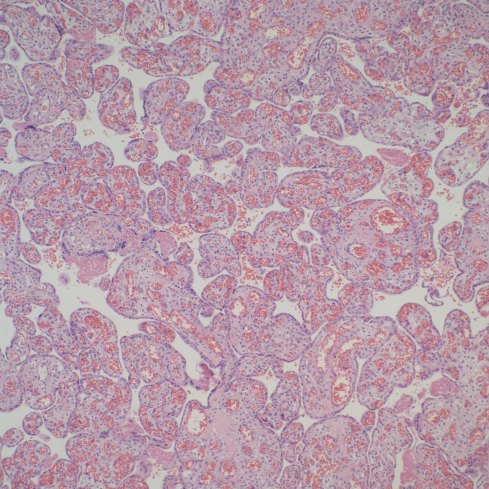

First I have trouble distinguishing hypervascularity in the villi from congestion which likely increases the apparent number of capillaries seen in microscopic cross section of a villus due to folding of engorged capillaries. Dr. Altshuler’s paper, warned of possible confusion between the two, and provided an illustration. Looking at his comparison photomicrograph in the paper I count at least 6 villi with more than 10 vascular profiles in the congested villi example. Given a photograph from a different area, that case might have qualified as chorangiosis. Many of the published papers illustrating chorangiosis in fact show villi with very dilated capillaries that do not give me confidence in the diagnosis[3-5]. To quote from a case review of chorangiosis: “Therefore, rigid diagnostic criteria were established by Altshuler (1984) for diagnosis of CH. These criteria, though difficult to apply, aim at differentiating CH from congestion(vessels numerically normal) and tissue ischemia (shrinkage of villi)…[6]”. The underline is mine. The acute capillary dilatation and probably increased blood flow over a retroplacental hemorrhage appears to increase the number of capillaries (fig) 1. This may explain the reported association of chorangiosis and abruption[7]. Perhaps congested villi with apparent hypervascularity should tentatively be a separate entity.

Distinguishing chorangiosis with its large terminal villi from persistent or increased intermediate villi is also not simple. I suspect that this confusion may be responsible for the association of maternal diabetes and chorangiosis. Dr. Ogino and Redline’s paper specifically mentions that the association is also with placentomegaly and delayed villous maturation. This problem can be seen clearly in looking at very early gestation placentas. (fig 2)